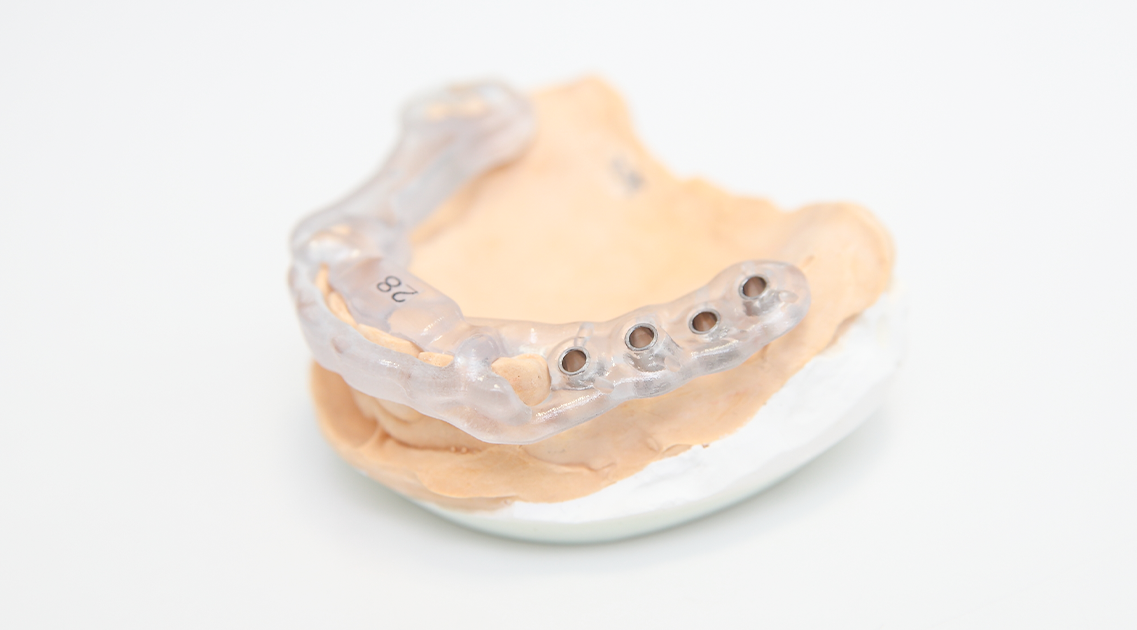

歯牙支持型フラップレス